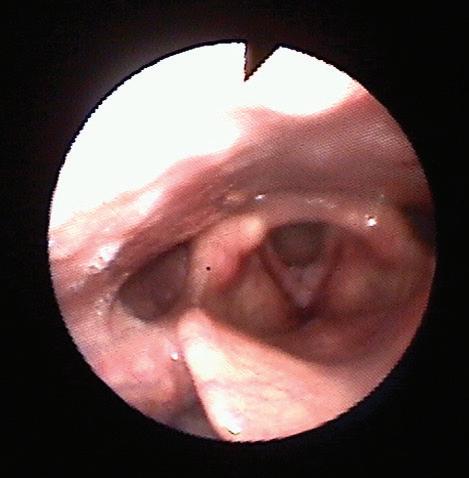

като засягане на ларинкса има при по -

от 95% от пациентите, при ларингоскопия се наблюдават характерните брадавицовидни формации (Фиг. 1. и Фиг. 2). Засягане на трахеята без ларингеални лезии се среща рядко и при тези случаи диагностичен метод на избор е бронхоскопията. Вземането на материал от лезиите за патохистологично изследване е от съществено значение за хистологично потвърждение на диагнозата. Биопсията е необходима както за типизация на вируса, така и за да се потвърди или изключи злокачествена трансформация.